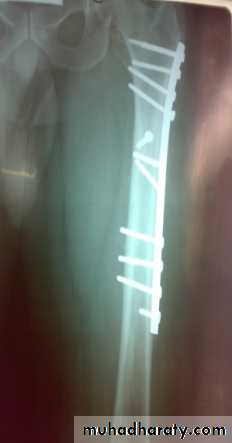

Definitive treatmentclosed fractures: by Open reduction and internal fixation, this will decrease the systemic complications.

fixation of femoral shaft fracture